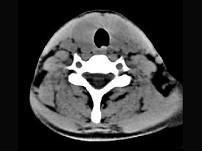

问题 40岁,女性患者,双侧甲状腺肿大,CT扫描如图所示,请选择最佳答案 ( )

选项 A、亚急性甲状腺炎 B、甲状腺瘤 C、甲状腺癌 D、甲状腺炎(桥本) E、弥漫性甲状腺肿

答案 D